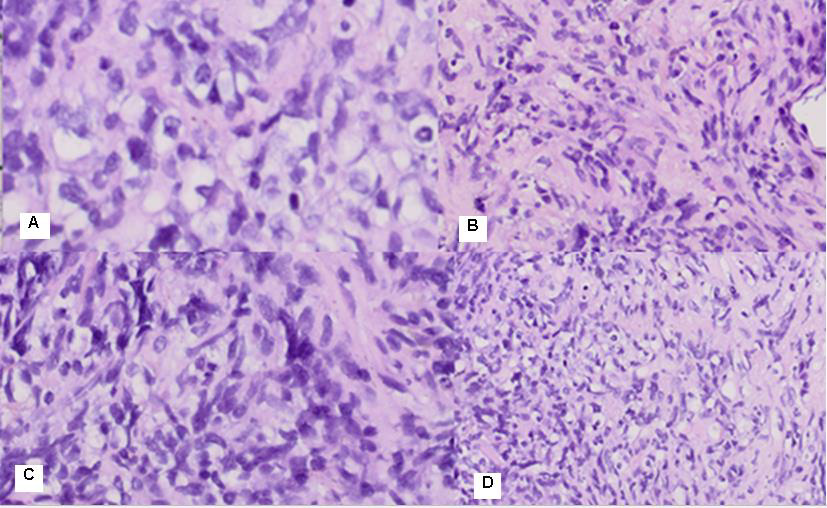

Figure 3: Photomicrography from the endoscopic biopsy of the stomach mucosa: А/ atrophic gastritis without a Helicobacter H&E: 20x; B/ Atrophic gastritis and Paneth cell metaplasia (PAS –Alcian blue): 20x; C/ Atrophic gastritis and Paneth cell metaplasia (PAS): 20x.

There is a slightly pronounced cell dysplasia in single glands, interstitial and Paneth cell metaplasia, hypertrophy of Muscularis Mucosae with chronically detected inflammation, corresponding to atrophic gastritis without Helicobacter pylori (Figure 3/A,B,C).